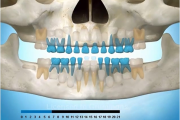

Esimeste molaaride (purihammaste) lõikumine

Esimeste molaaride (purihammaste) lõikumine. 1. molaaride ektoopilise lõikumise jälgimine. Ülemised ja alumised esimesed purihambad e. molaarid lõikuvad orienteeruvalt6-7-aastaselt piimahammaste rea lõppu. Enamasti lõikuvad samanimelised jäävhambad paaridena. Normaalne lõikumise Loe edasi »

- valehambumus (18)